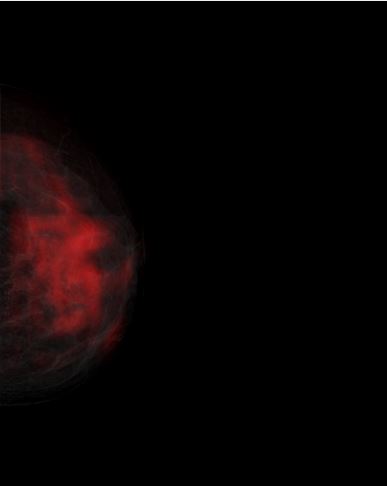

A Glimpse of CAD Functionalities On Preloaded Real Digital Mammograms

Raw Mammogram

Figure (1)

Raw digital mammography CC view